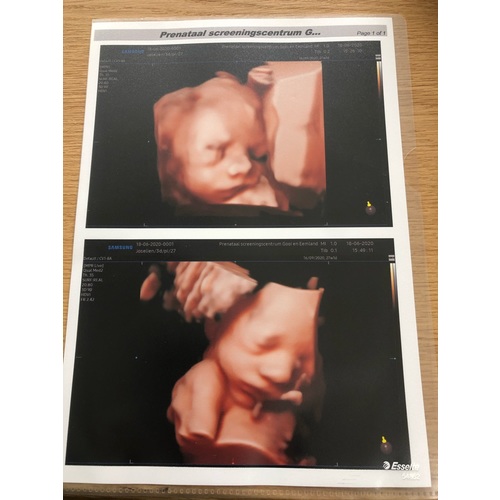

5 jaar geleden

Wij hadden 'm ook met 28 weken. Ons meisje lag al vrij laag met het hoofdje en zat met de linkerkant van haar gezichtje in de placenta gedrukt. En ze hield haar arm steeds voor haar mond. Af en toe piepte ze er boven uit en liet ze zich even zien. Het waren kleine momentjes, waarop we haar zagen gapen, lachen en drinken. Hoewel ik heel veel mooiere foto's gezien heb op dit forum, was het voor ons ondanks de slechte ligging een onvergetelijk mooie ervaring en zou ik het iedereen aanraden!